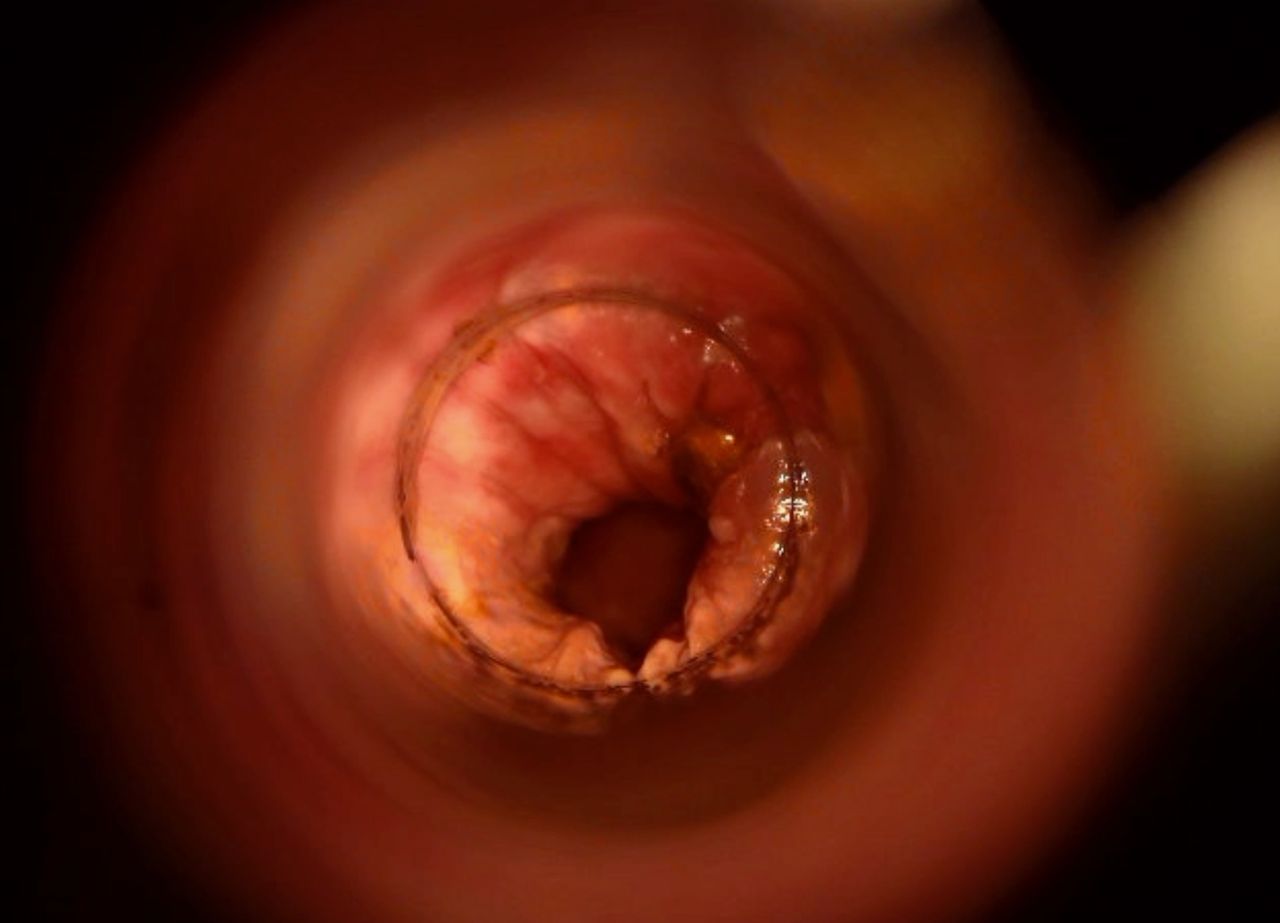

La cura delle emorroidi patologiche, finalmente senza dolore

Come Chirurgo Vascolare, sono perfezionata in Proctologia da molti anni, e molti altri ne ho passati direttamente in sala operatoria, praticando l'emorroidectomia con metodo Milligan-Morgan.

Durante la mia esperienza come Chirurgo Protcologo, ho visto personalmente come i trattamenti chirurgici disponibili, benché necessari, fossero comunque abbastanza invasivi per il paziente, specialmente nel decorso post operatorio.

Fortunatamente, negli ultimi anni sono stati messi a punto protocolli non chirurgici molto avanzati, che ho personalmente studiato ed approfondito con molto interesse.

Tra questi, ho cominciato ad utilizzare il trattamento sclerotizzante con scleromousse stabilizzata ad aria sterilizzata, che considero ormai il 'Gold Standard' per il trattamento non invasivo e permanente delle emorroidi patologiche.

Ho quindi attrezzato il mio studio con il moderno Videoproctoscopio Digitale, nonché con avanzate pompe miscelatrici ad aria sterilizzata, in grado di ottenere una scleromousse stabilizzata di grande qualità, perfetta per il trattamento emorroidale.

Grazie a questo protocollo, posso risolvere casi anche molto gravi di prolasso emorroidale, garantendo una risoluzione definitiva in oltre il 95% dei casi clinici.

Il tutto, senza il minimo dolore o disagio per il paziente.